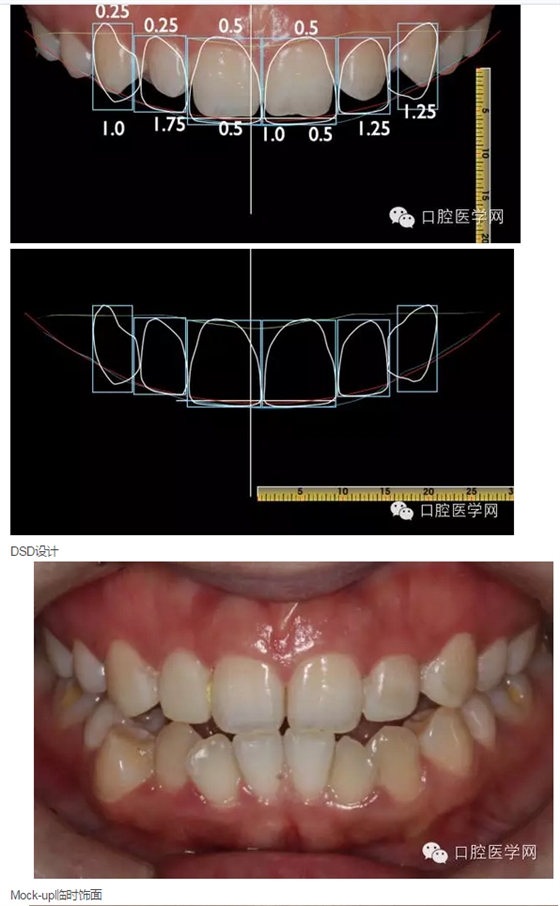

計劃先拍攝分析照片、制取分析模型,通過數(shù)字化微笑設(shè)計(Digital Smile Design)分析患者存在的美學(xué)為題,展示美學(xué)修復(fù)后的大致效果,并指導(dǎo)技師完成美學(xué)蠟形設(shè)計(Wax-up);再通過美學(xué)蠟形在口內(nèi)翻制臨時(DMG)樹脂飾面,讓患者更加直觀的看到美學(xué)修復(fù)后的效果,參與設(shè)計,檢查咬合,在臨時飾面基礎(chǔ)上進(jìn)行常規(guī)定深備牙,最后根據(jù)共同研究修改后的形態(tài)制取參考模型指導(dǎo)最后的修復(fù),以達(dá)到良好的美學(xué)修復(fù)效果?;颊邔υ锨把赖念伾袧M意,故不考慮遮色,選擇更加微創(chuàng)、通透美觀的烤瓷貼面修復(fù)。

2015年3月28日:展示DSD設(shè)計,探討美學(xué)修復(fù)方案(見圖10-15),取模制作美學(xué)蠟形。